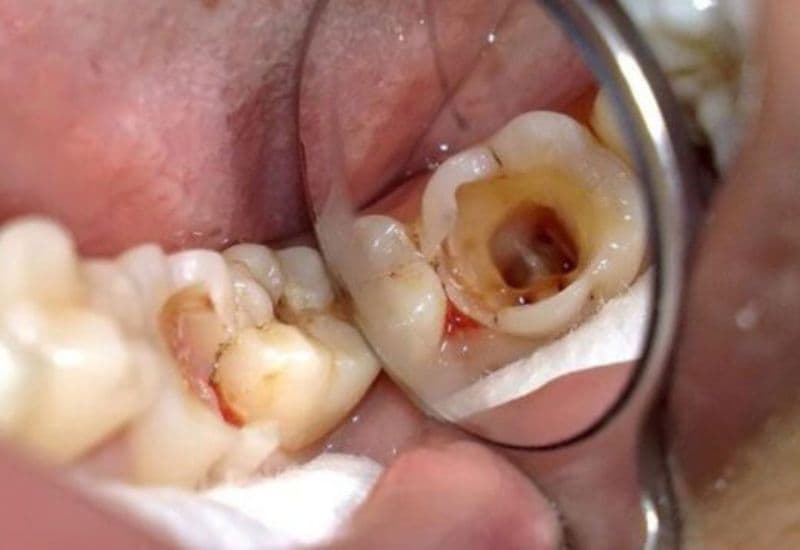

Sâu răng hở tủy là giai đoạn nặng của bệnh sâu răng, khi vi khuẩn ăn mòn men răng và ngà răng, tiến sâu vào buồng tủy, khiến tủy răng bị lộ ra ngoài. Đây là một tổn thương nghiêm trọng vì tủy răng là nơi chứa nhiều dây thần kinh và mạch máu nuôi dưỡng răng. Khi tủy bị hở, người bệnh sẽ cảm nhận rõ rệt các triệu chứng như:

– Lỗ sâu lớn, dễ thấy bằng mắt thường: Quan sát kỹ có thể thấy lỗ sâu to, đen hoặc nâu sẫm, bề mặt răng sần sùi, dễ mắc thức ăn.